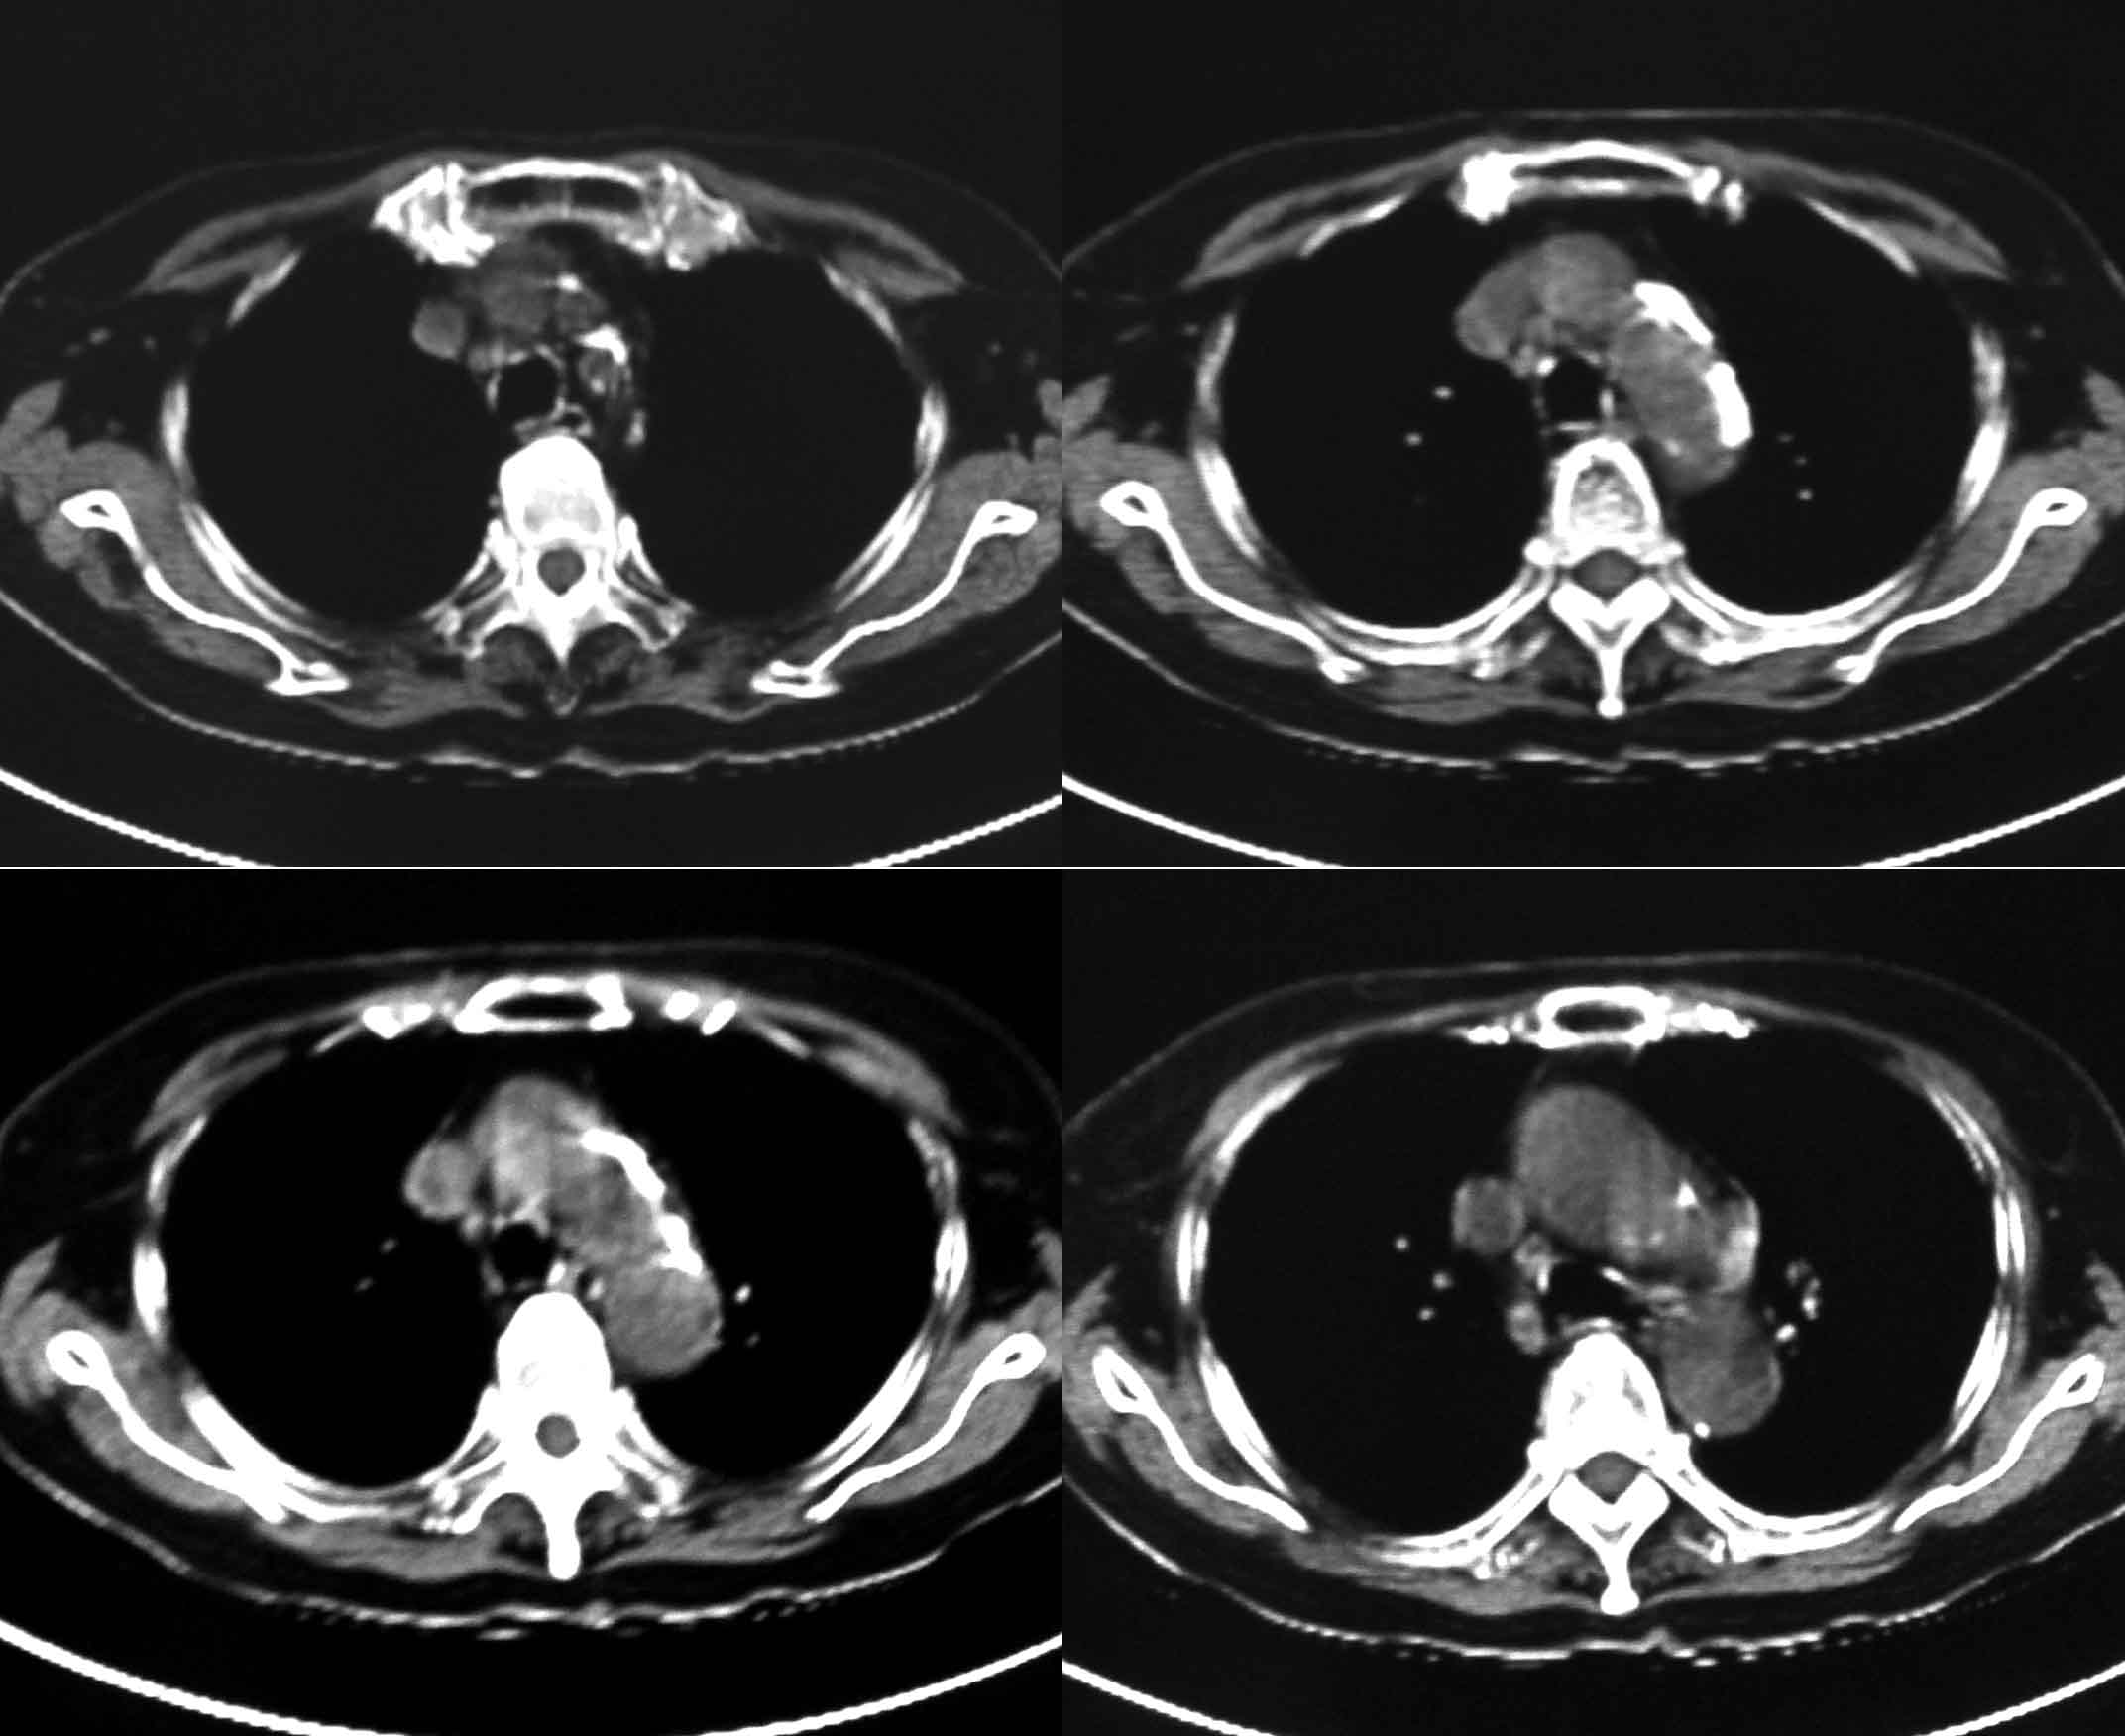

女69岁。时有咳漱、咳白色痰请老师们看看箭头所指是什么?ct值约-36.报告应该怎样写?谢谢!

考虑左后下胸内侧壁与胸膜之间脂肪影。

左后下胸内侧壁与胸膜之间脂肪影。

考虑左后下胸内侧壁与胸膜之间脂肪影。支持

胸膜下脂肪影。